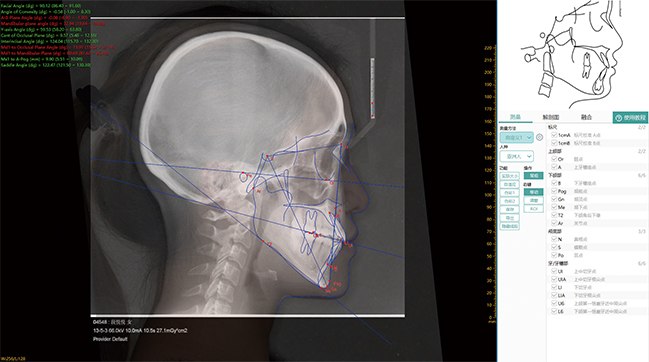

Medición cefalométrica

- Más de 100 elementos de medición y 14 grupos de planes de medición

- Dibujar diagramas de estructuras anatómicas y aplicar plantillas directamente

- Fusión precisa de diagramas anatómicos, radiografías laterales e imágenes planas.

- Combinación personalizada, medición fácil